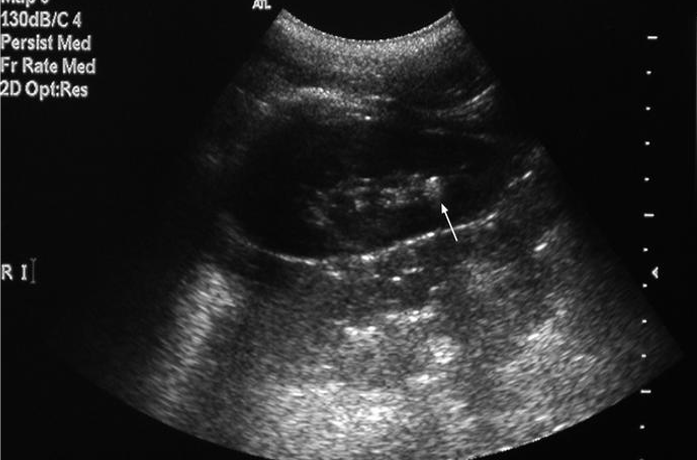

Lesiones focales

El hallazgo de una lesión ocupante de espacio o lesión focal en la ecografía hepática puede producirse de manera fortuita durante un estudio abdominal realizado por otro motivo o aparecer al investigar la causa de una hepatopatía o al realizar el screening de hepatocarcinoma en un paciente cirrótico. Hay que